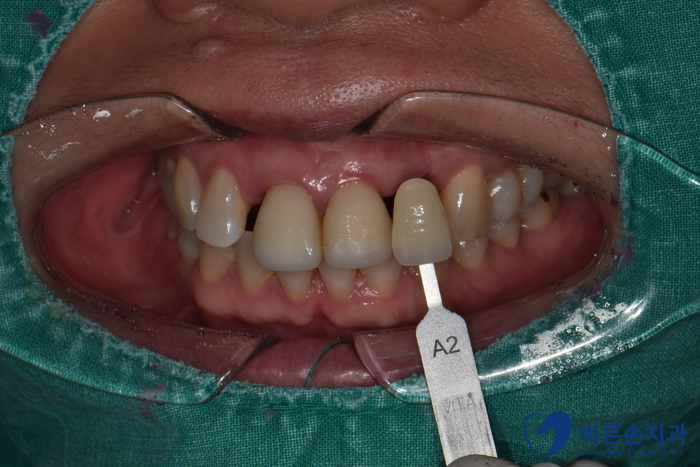

치아색 확인 후 3D 구강스캐너로

보철을 만들어 옵니다!